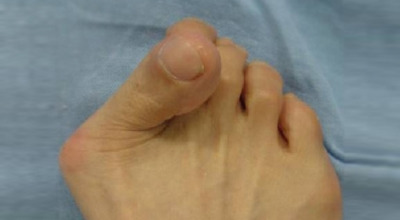

엄지발가락이 두 번째 발가락 쪽으로 과도하게 휘고, 엄지발가락과 연결되는 중족골이 반대로 안쪽으로 기울어지며 발가락이 발등 쪽으로 휘거나 회전(엄지발가락 축을 중심으로 내측으로 회전; 회내)하는 삼차원적인 변형을 말합니다.

무지외반증이 심해지면 엄지발가락이 두 번째 발가락과 겹치거나 관절이 탈구되어 전반적으로 발을 디디기 어려운 상태가 될 수 있습니다. 건강보험심사평가원의 무지외반증 환자 통계에 따르면, 40대 이상에서 가장 많이 발생하며, 여성 환자 비율이 남성보다 월등히 높다고 합니다.

육안으로 확연히 엄지발가락의 변형이 보이며, 초기에는 굳은살이 생기고 약간의 통증도 동반됩니다. 엄지발가락의 돌출 부위에 통증이 발생하는데, 이 부위가 신발에 자극을 받아 두꺼워지고 염증이 생겨 통증이 유발됩니다. 발바닥에 굳은살이 생기면 정상적인 보행이 어려워지고, 심한 경우에는 통증 때문에 신발 착용이나 정상적인 보행도 힘들어질 수 있습니다. 증상이 지속적으로 악화되면 엄지발가락이 겹치거나 탈구될 수도 있습니다.